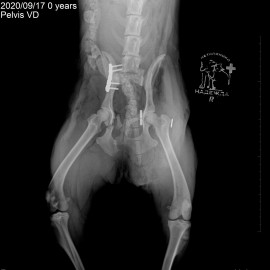

Собака по кличке Белла из города Мурманск. Её сбила машина. после чего были жалобы на потерю опороспособности на тазовые конечности. При пальпации живота отмечался дефект. После проведения рентгенологического исследования были поставлены диагнозы: вывих правого тазобедренного сустава, травматическая грыжа живота, множественные переломы костей таза. Были проведены операции: остеосинтез костей таза, остеосинтез правого тазобедренного сустава (установлен протез круглой связки), герниотомия травматической грыжи живота.

Снимок 3 после операции.